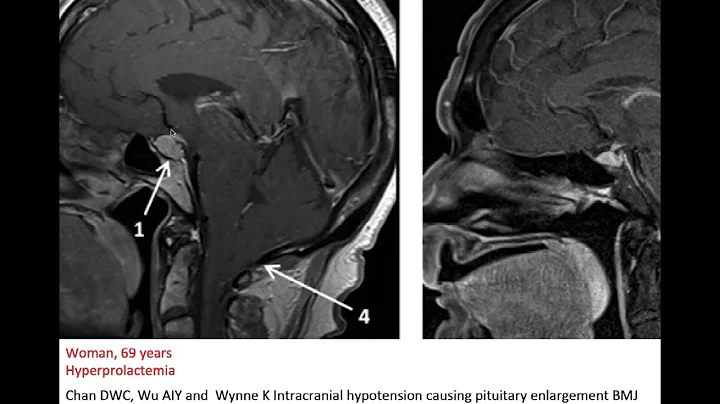

Intracranial Hypotension (radiopaedia.org) Cases In Radiology

Link to case: https://radiopaedia.org/cases/intracranial-hypotension-29?lang=us.